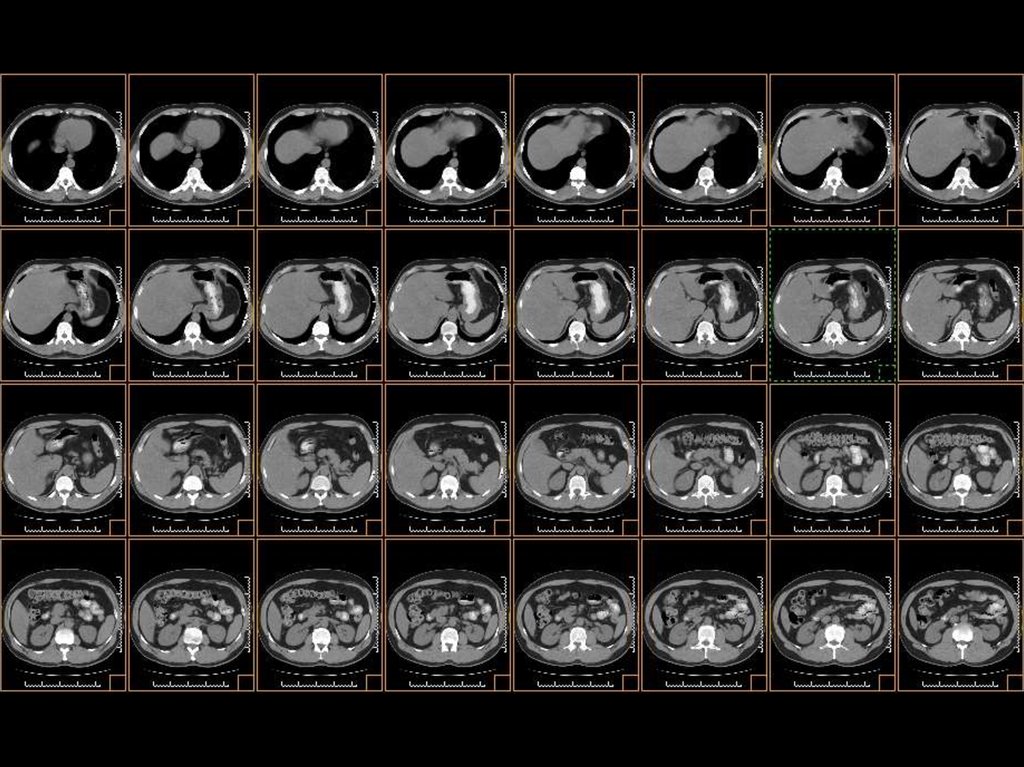

исследование брюшной полости

Ток: 300 мА

Напряжение: 120кВ

Толщина среза: 5.0 мм

Матрица: 512х512

Режим: спиральный, 11.25 мм/с